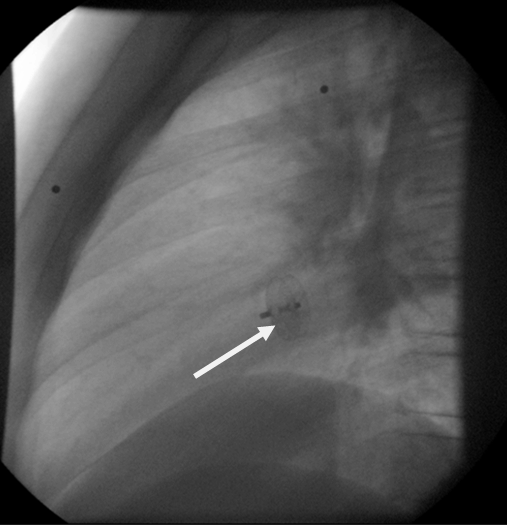

Consequently, a digital subtraction angiography (DSA) from the femoral artery was performed which did not reveal underlying vascular abnormalities (Figure 4).

Due to the relative contraindication for thrombolysis, patient was initiated immediately on anticoagulation therapy with low molecular weight heparin and warfarin. Two days later, she developed acute symptoms of dyspnea and chest pain and a subsequent spiral thorax CT scan revealed pulmonary emboli at the left pulmonary artery, as long as the persistence of the atrial thrombus. Anticoagulation therapy was continued and a foramen ovale umbrella placement was later performed (Figure 6).

Figure 4: Digital subtraction angiography imaging, revealing no pathological findings.

Figure 6: The arrow indicates the site of placement of the umbrella.